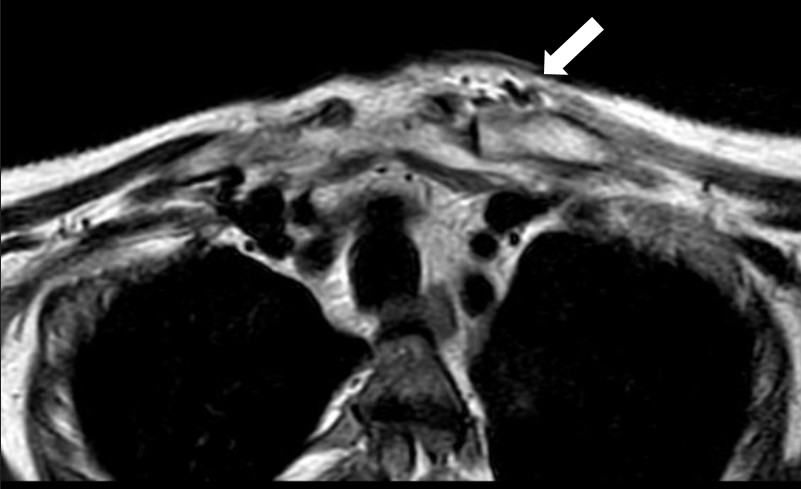

MRI of the chest showed findings consistent with osteomyelitis, including bone irregularities, edema, subchondral erosions of the right sternoclavicular joint, synovitis, and inflammatory joint changes (Fig. 2- 4).

Figure 3. Axial magnetic resonance imaging. Lytic lesion with periosteal reaction characteristic of osteomyelitis.